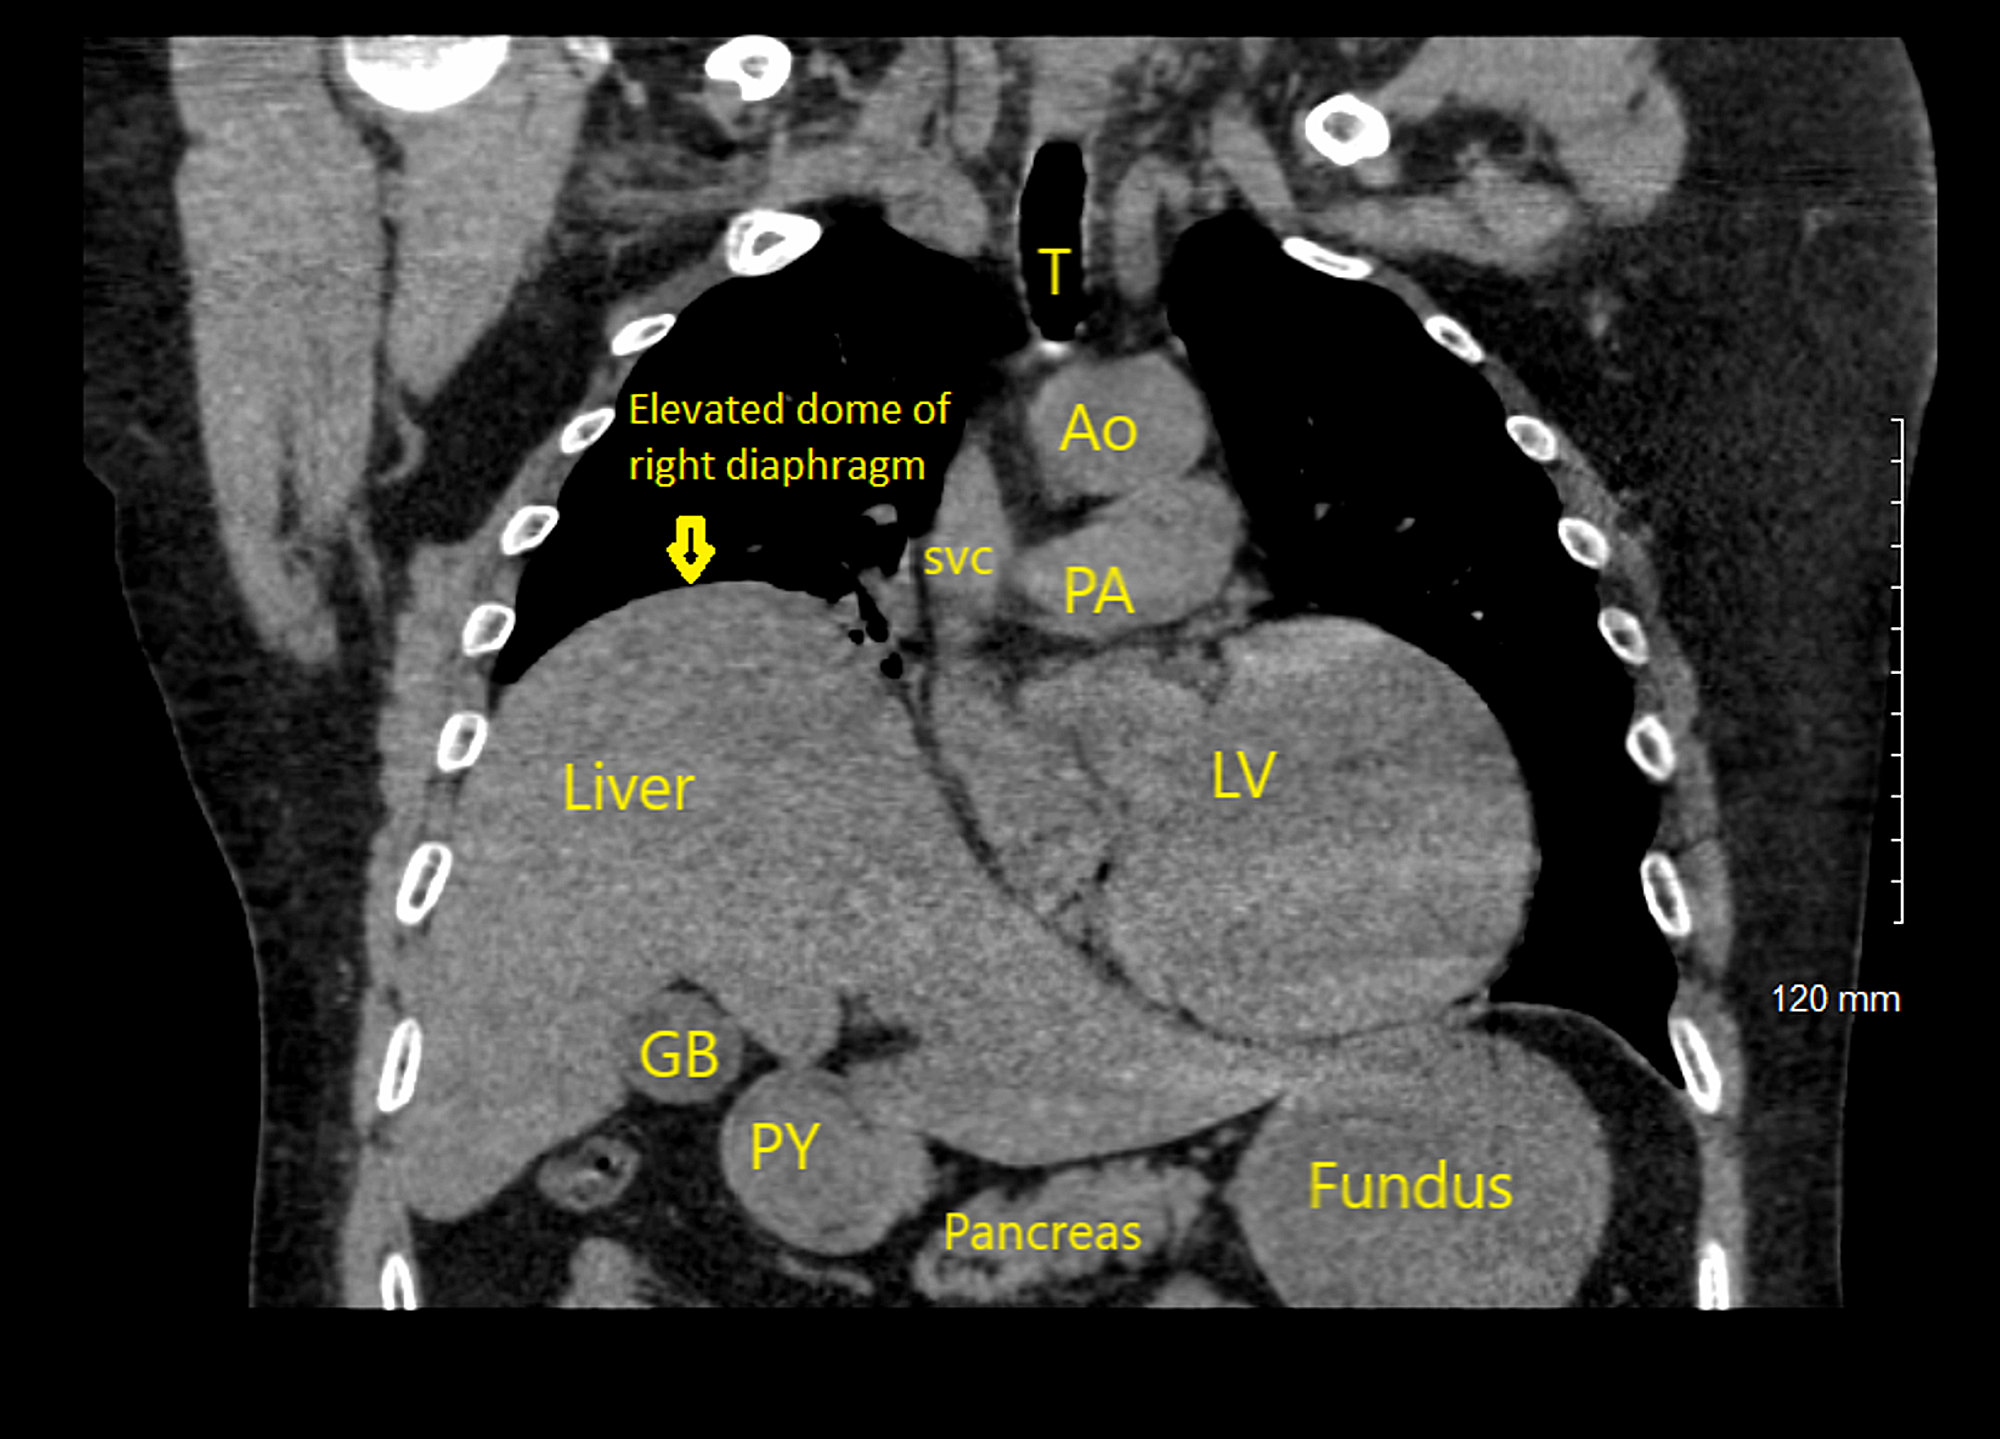

Pneumoperitoneum and subphrenic abscess are two important differential diagnosis of this radiographic sign which can be excluded out when normal plicae circulares or haustral markings of the colon is seen under the right diaphragm. If youre experiencing mild discomfort in your diaphragm take a few minutes to concentrate on deep breathing. Treatment depends on the type of hiatal hernia you have and on your symptoms.

Place one hand on your abdomen and breathe deeply. Reduced number of alveoli air sacs required for normal breathing. In severe cases when there is no simple treatment that can relieve dyspnea your doctor may prescribe morphine. Congenital diaphragmatic hernia CDH. There is usually a long history of heavy smoking. Shortness of breath may be accompanied by wheezing. Diaphragmatic dysfunction caused by transverse myelitis or leukemic infiltration of the cervical spinal cord in a patient with leukemia and shortness of breath. To treat phrenic nerve irritation This condition can be managed with a breathing pacemaker which takes over the responsibility of sending messages to the diaphragm. The cause for shortness of breath was thought primarily due to stable angina on tread mill test positive finding but Chilaiditis syndrome should also be considered as a cause for the shortness of breath.

The rise in intraabdominal pressure further increases intrathoracic and lung volume by pushing the lower rib cage outward. In severe cases when there is no simple treatment that can relieve dyspnea your doctor may prescribe morphine. Diaphragmatic dysfunction caused by transverse myelitis or leukemic infiltration of the cervical spinal cord in a patient with leukemia and shortness of breath. Diaphragmatic plication a surgical procedure that pulls the diaphragm down by introducing a repeated series of continuous sutures across the diaphragm and pulling the muscle taut. A bedside fan or open window with a breeze are also simple but very effective treatments to lessen dyspnea. Depending on the severity of injury to the diaphragm some doctors recommend non-surgical options to treat the breathing issues associated with diaphragm weakness and paralysis. P E Pulmonary embolism.